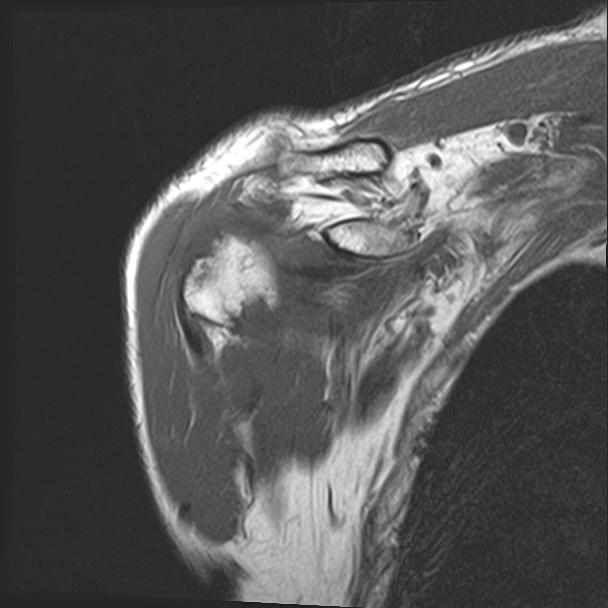

60058 3/9 11/4 右肩 2R+MRI 73歳男性 肩腱板損傷